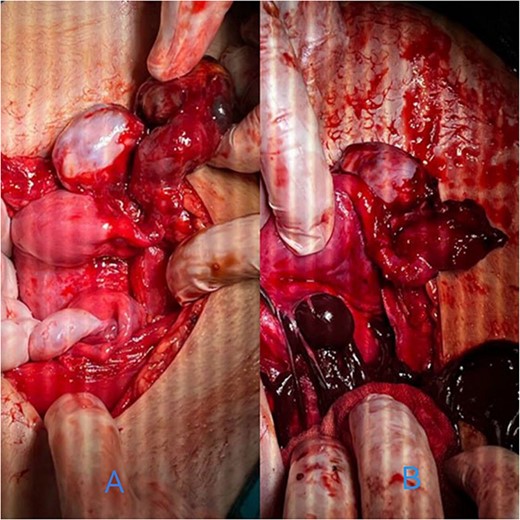

By surgically opening and reaching the abdominal cavity, two uteruses were found, along with a mass filling the pelvic cavity, measuring about (8 × 7 cm). We also saw a didelphys uterus with normal right and left ovaries, a hematoma filling the left fallopian tube, and an accumulation of blood within the vagina (hematocolpos) (Fig. 3).

(A) A hematoma in the left fallopian tube. (B) An accumulation of blood in the vagina.